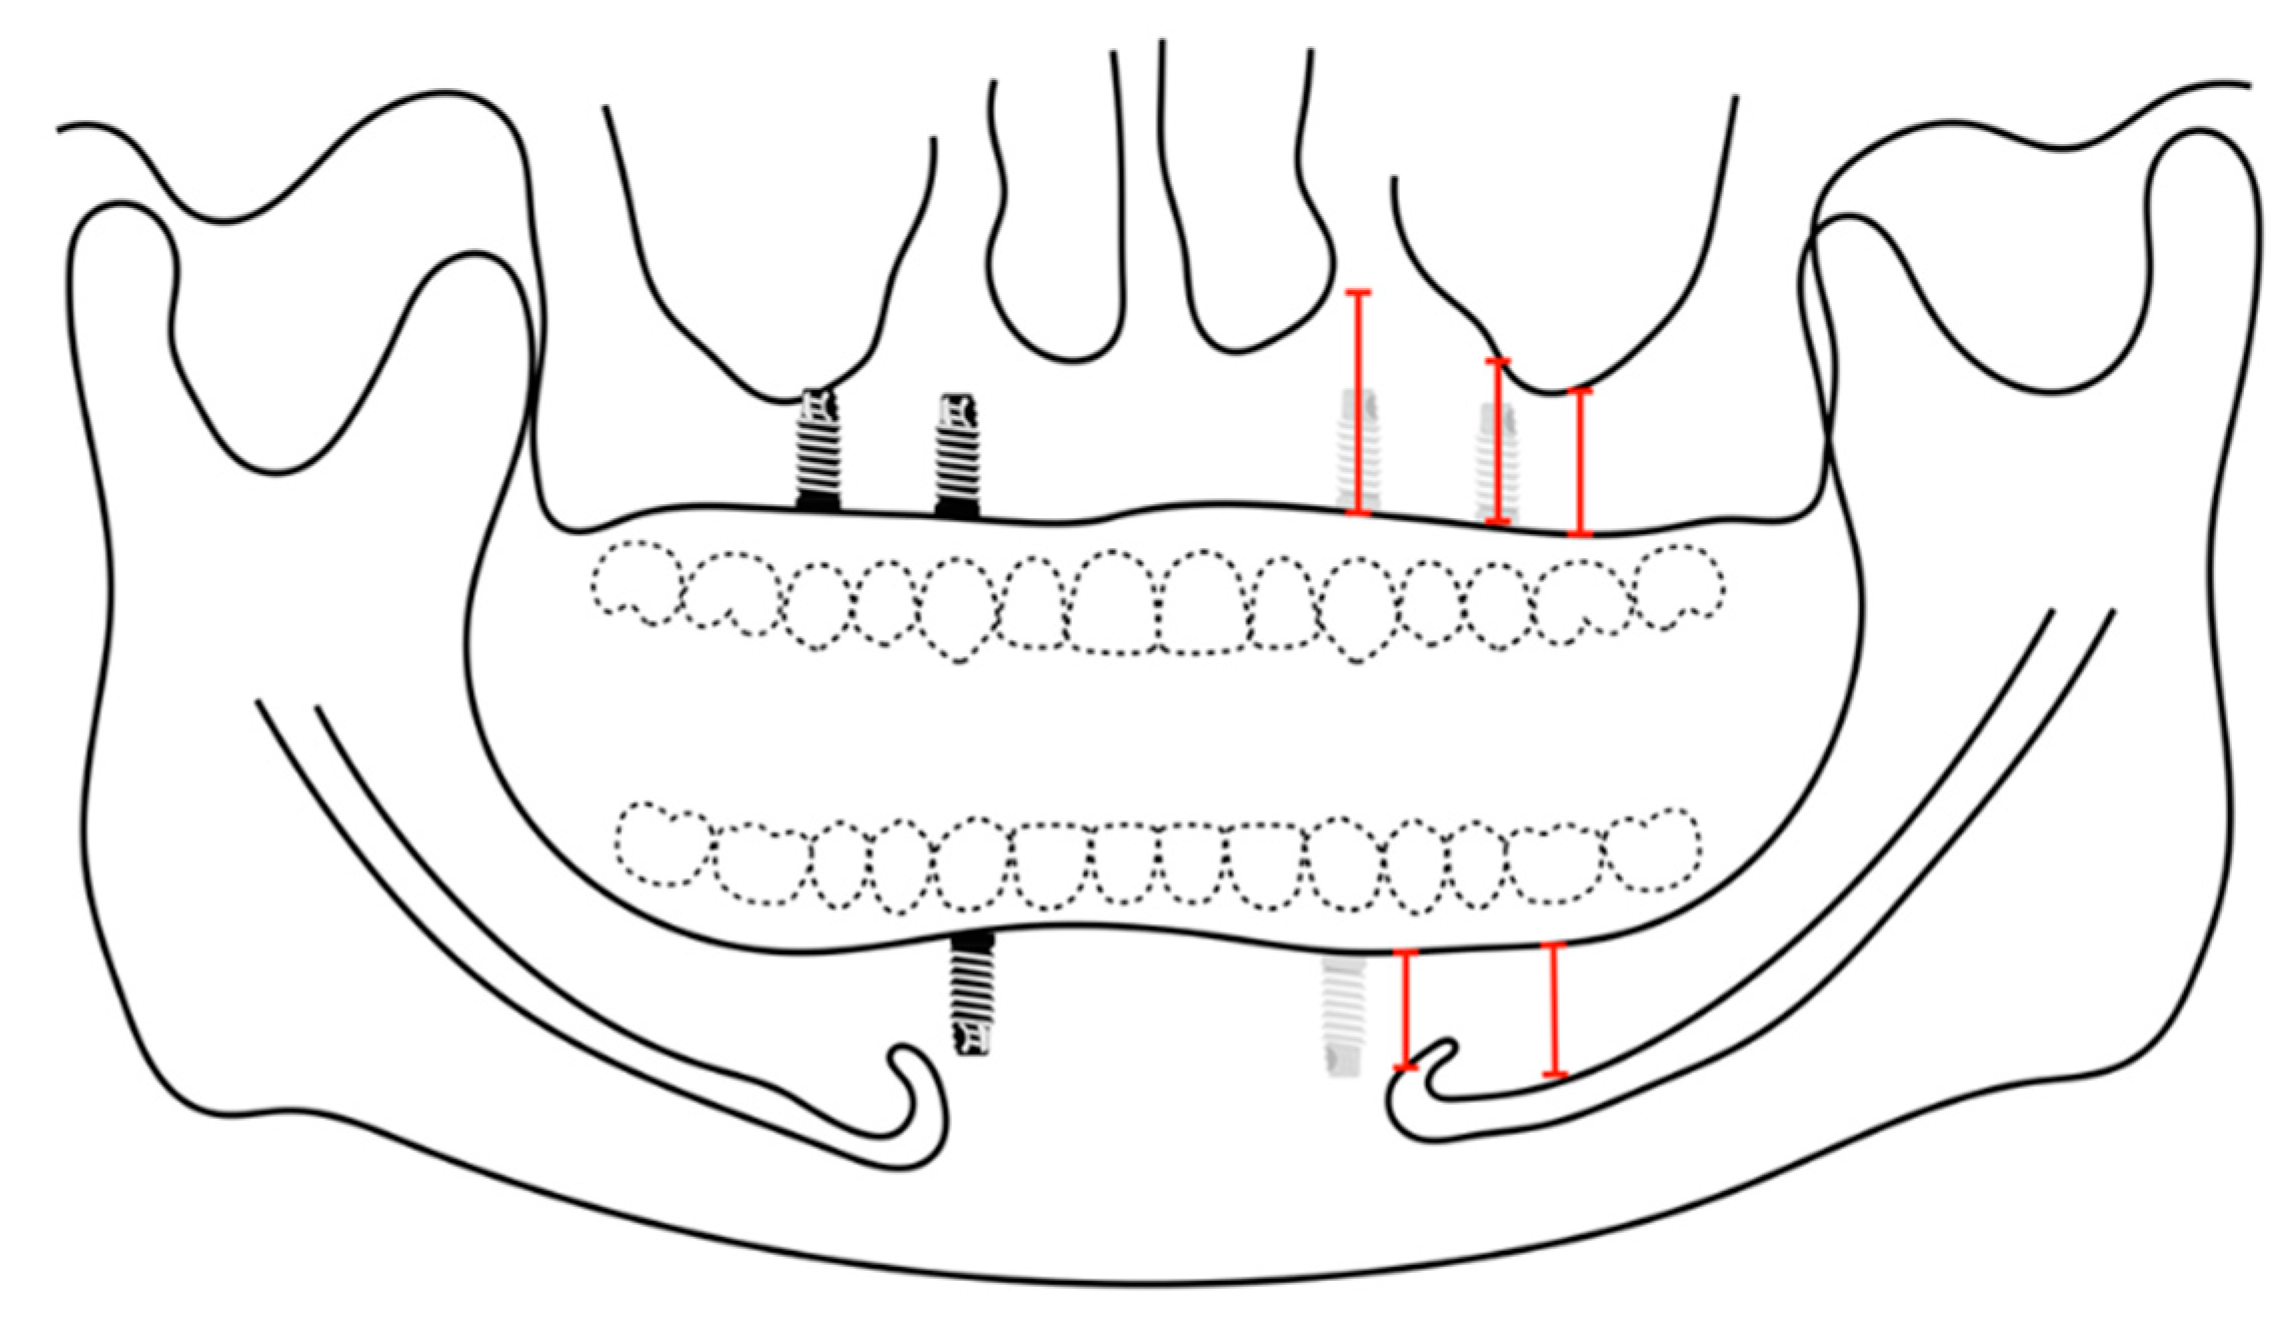

The examiners had digitally measured the alveolar ridges of 4 implant sites in the maxilla and 2 implant sites in the mandible to place implants for an implant-supported removable prosthesis for both maxillary and mandibular arches (Figure 6). Four implants are planned for the removable prosthesis at the laterals or canines, and the second premolars areas for the maxilla. Two implants at the area of the canine for the mandible. The surgical sites are investigated if they require additional augmentation procedures in advance or afterward, whether guided bone regeneration (GBR) or sinus elevation. Each site at the data collection sheet was given a number, the following numbers were considered and standardized when performing the digital planning:

Figure 6. Digitally planned implant and the anatomical analysis. Four implants (the area of lateral incisor canines, second premolars) are planned on the maxilla for implant-supported overdenture. Two implants (the area of canine) are planned on mandible for implant-supported overdenture.